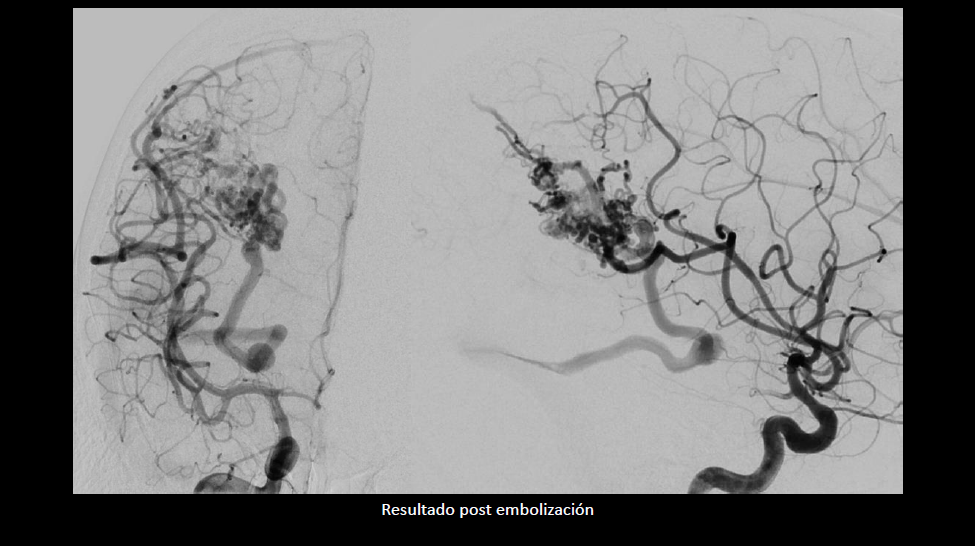

Tratamiento combinado de malformación arteriovenosa con sangrado reciente